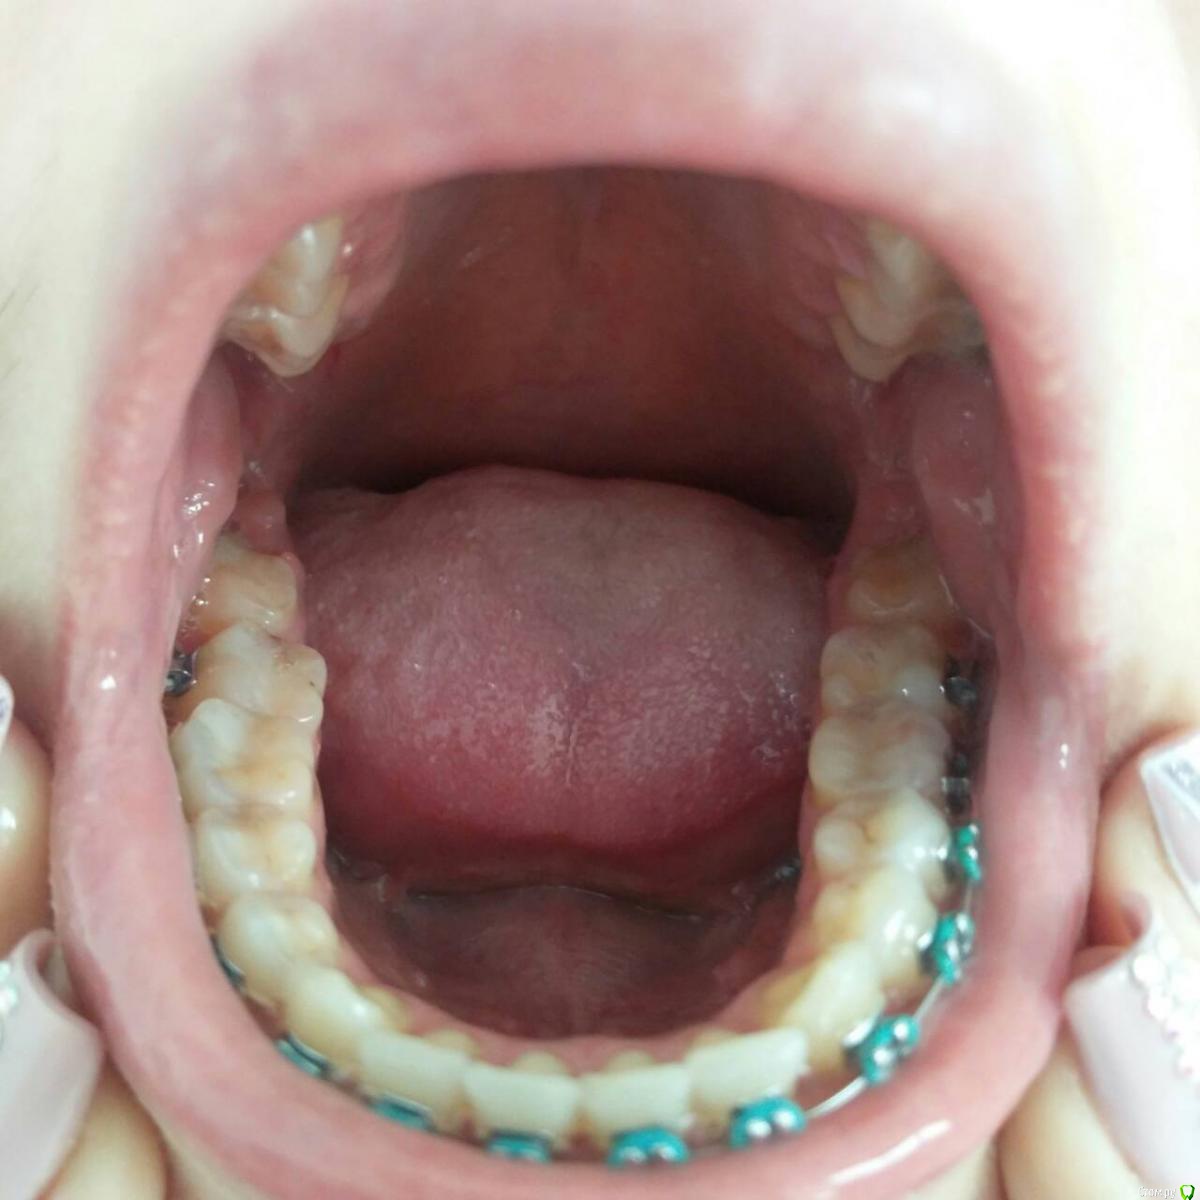

Валг Опубликовано 31 августа, 2018 Поделиться Опубликовано 31 августа, 2018 Добрый день!Нужен совет по поводу исправления прикуса, перекрестный, 3 класс, но точно я не уверена, врач мне мало что разъяснил. Ношу уже 4 месяца, и теперь врач мне говорит что нужно удалять нижние 5, так как они мешают смыканию челюстей и зубы вынуждены сильно наклонятся вперёд.Изначально ортодонт говорил, что удаление зубов не потребуется. Посоветуйте, пожалуйста, что делать! Ссылка на комментарий

Валг Опубликовано 31 августа, 2018 Автор Поделиться Опубликовано 31 августа, 2018 Мои фотографии Ссылка на комментарий

Kazankov.Egor Опубликовано 1 сентября, 2018 Поделиться Опубликовано 1 сентября, 2018 Как минимум, я бы сейчас остановился: смущает то, что на ОПТГ (снимок всех зубов) центры зубных рядов более-менее совпадают, скорее всего это проблема зубных контактов, которые имеются на данный момент. Первое - депрограммирование челюсти. По остальному: нужно видеть фото полные внутриротовые и модели "до" и "на этапе". Ссылка на комментарий